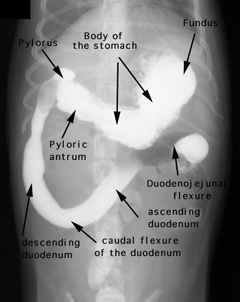

Barium was administered orally and the radiographs were taken 5 minutes later